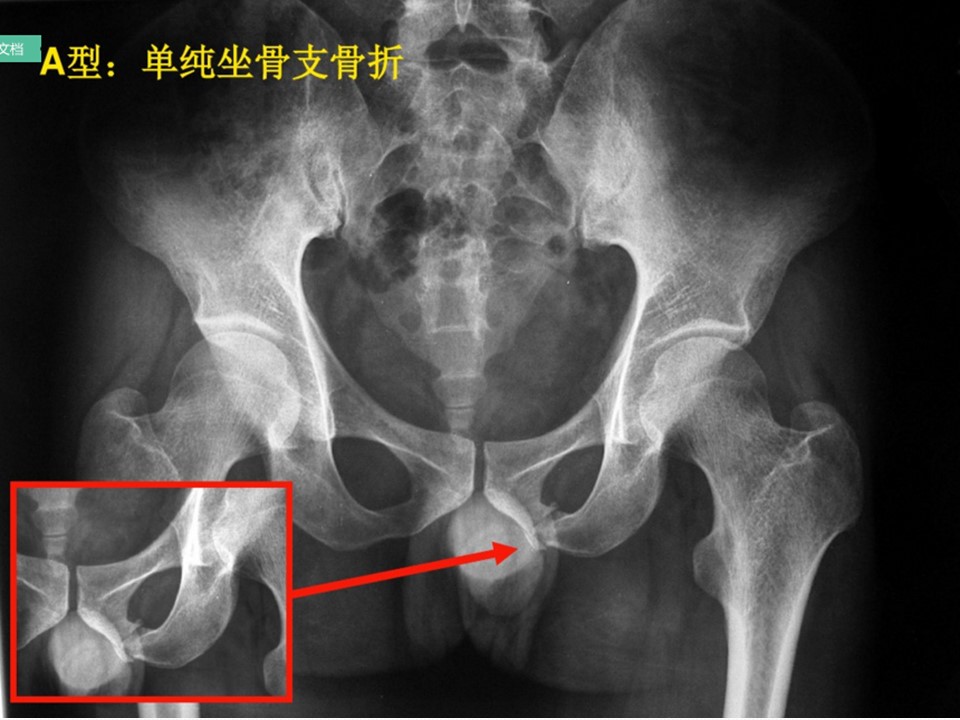

骨盆骨折PPT

稳定性骨折:低能创伤所造成的骨盆骨折

多发生于老年人跌倒及低速车祸,或未成年人及运动员

不稳定骨折:多由高能外伤所致。据统计,骨盆骨折中50%~60%由汽车车祸造成,10%~20%是由于行人被撞,10%~20%为摩托车外伤,8%~10%为高处坠落伤,3%~6%为严重挤压伤。